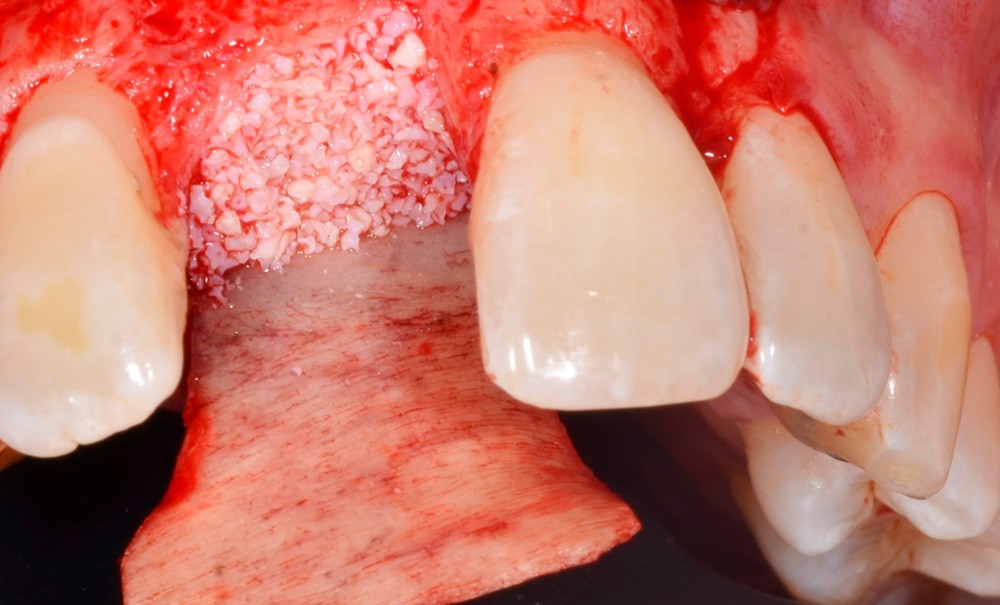

Dans les situations favorables, cet acte chirurgical intéresse a minima les tissus gingivaux et osseux maxillaires. Dans les situations de volume osseux réduit, la mise en place de l’implant s’accompagne alors d’une régénération osseuse qui accroît l’invasivité de l’acte.

• pose d’implant(s) associée à une régénération osseuse guidée (ROG).